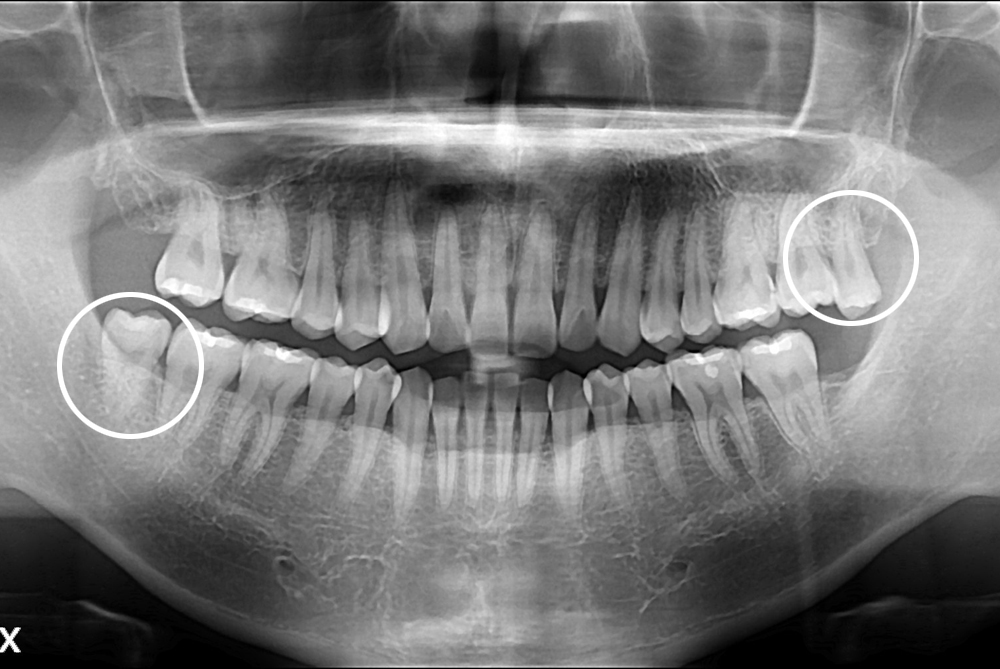

[사랑니] 난발치 사랑니 발치

치료전 : 2017-02-15